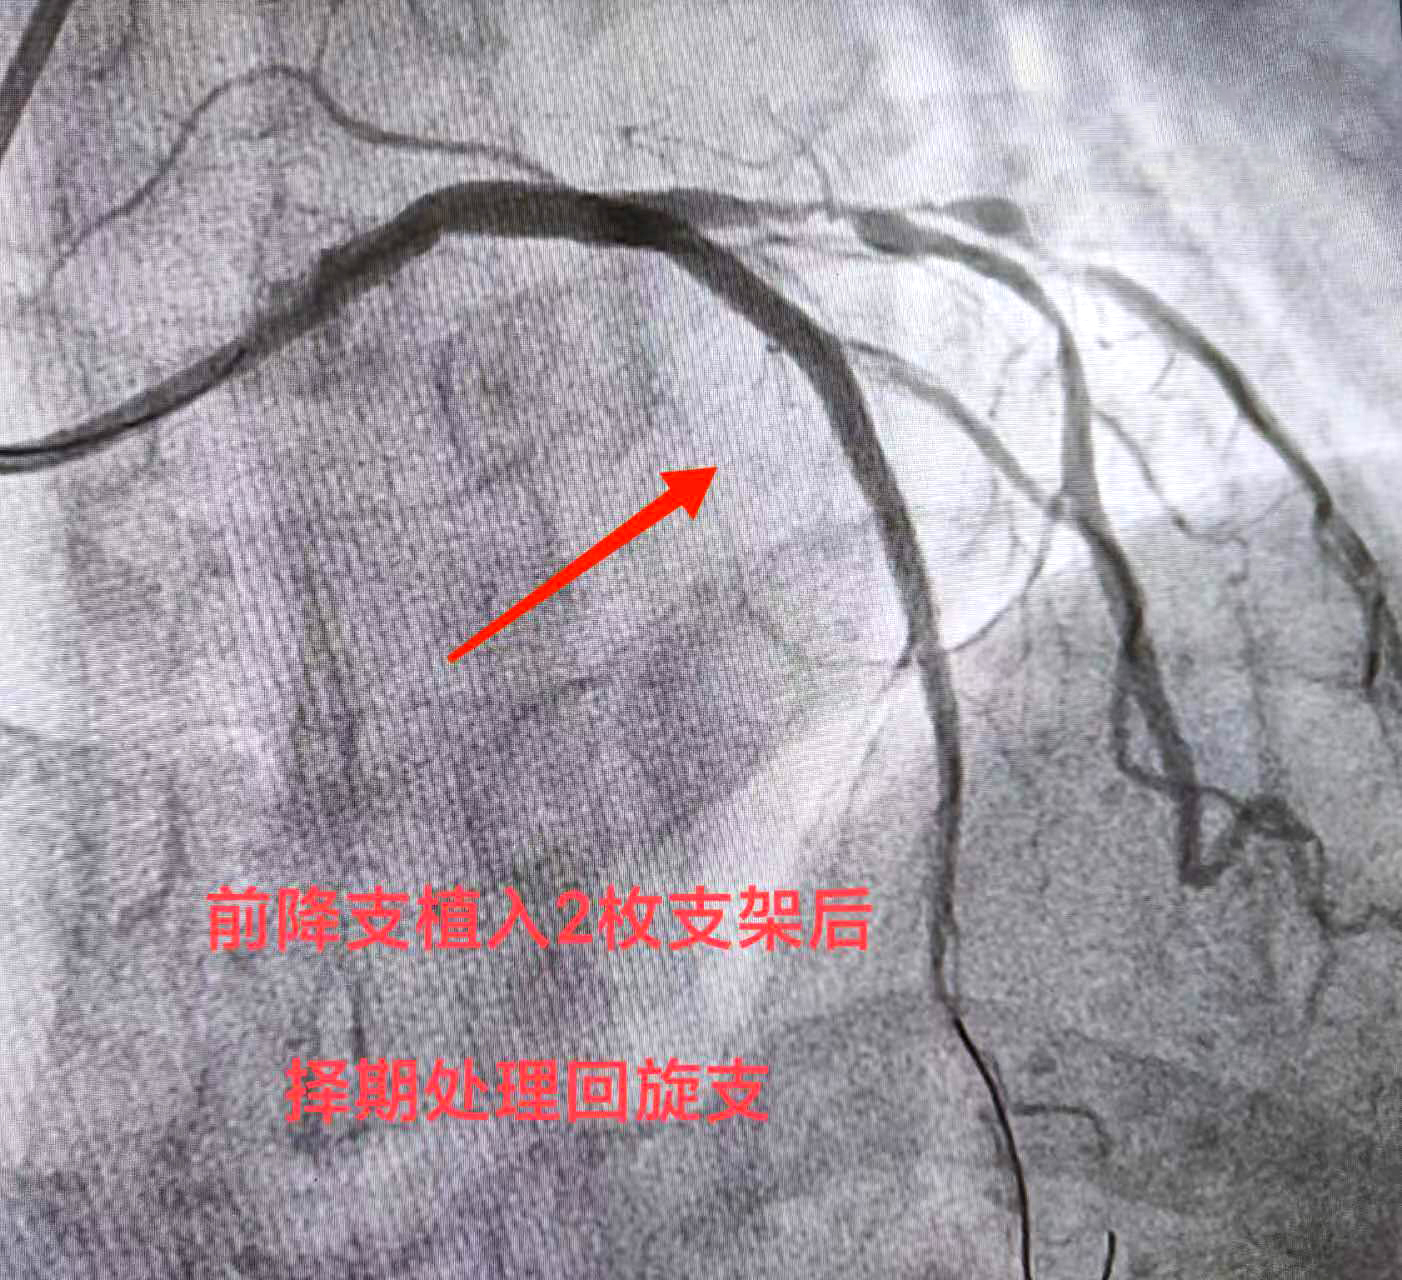

经检查,赵某恢复良好,身体状况符合再次开展介入的条件,因此医院很快为赵某安排了手术时间。“依据我们根据患者病情制定的治疗方案,这一次针对前降支血管开展支架介入。”熊斌主任介绍,根据赵某的血管具体情况,此次介入仍是在杨胜利教授的指导下,在赵某的前降支血管植入两枚药物洗脱支架,支架贴壁膨胀良好,血管得以顺利开通,血流得以恢复,而且支架上携带的药物也能起到预防支架内再狭窄的作用。同时,科室在脉络学说指导下,发挥中西医结合诊疗优势,在常规西药加支架治疗基础上加用通络药物,显著降低心梗支架术后心肌无复流发生率,改善心肌微循环血液灌注,保护心肌,减少心室重构,避免向慢性心衰发展,从而改善心梗支架植入患者的远期预后。

“通过两次支架介入,患者已实现狭窄血管再重塑,血流改善,心血管风险大大降低。”熊斌主任表示,待赵某恢复调养一段时间后,则可再针对回旋支血管进行介入开通,这将会进一步改善心脏供血,缓解相关不适症状。